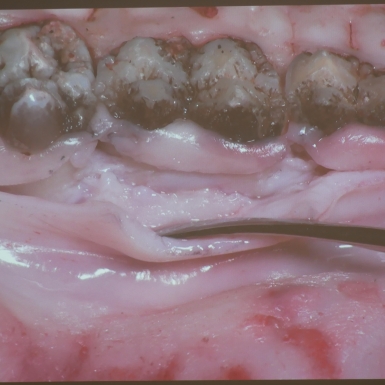

Terapia resekcyjna [19-21.01.2023]